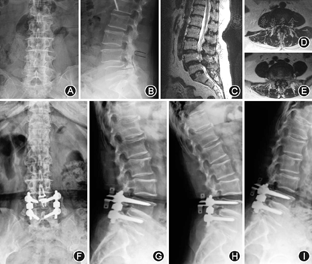

两组术前Coflex植入节段椎间隙高度、椎间孔高度、椎间孔宽度和ROM差异无统计学意义(P>0.05)。Topping-off组椎间孔高度、椎间孔宽度、椎间隙高度术后1年随访较术前显著增加,但末次随访相比术后1年显著降低,与术前无显著性差异。融合组椎间隙高度、椎间孔高度和宽度在术后各随访时间点无显著性改变。融合组术后椎间活动度显著性降低(P=0.000)(图2,图3)。

末次随访Topping-off组上位邻近节段椎间孔高度和椎间隙高度较术前降低,但是两组间差异无统计学意义(P>0.05)。融合组上位相邻节段末次随访椎间孔高度、椎间隙前缘高度和椎间隙后缘高度较术前显著性降低(P=0.000, P=0.000,P=0.003),并且ROM由术前的(4.4±2.7)°显著性的增加到(5.4±2.2)°(P=0.000)。末次随访对两组患者下位邻近节段各指标与术前差异无统计学意义(P>0.05)。